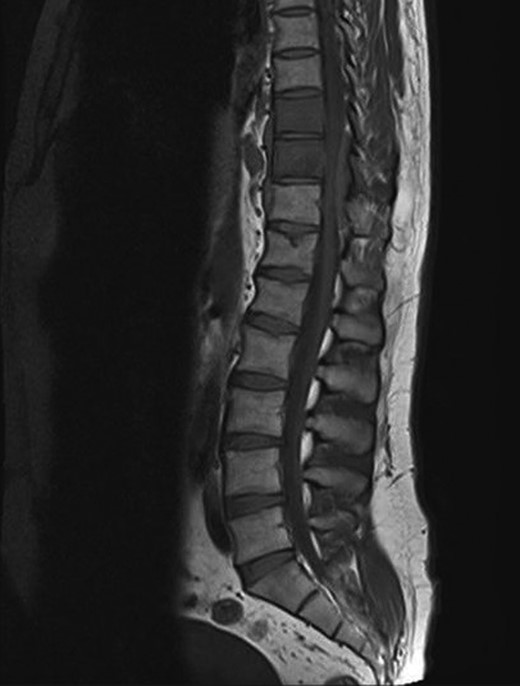

A 30-year-old male patient was admitted to our clinic with back pain. Pain was provoked by movements. The severity of pain was associated with the inability to perform the activities of daily living. The patient did not have any lymphoma-related B-type symptoms, including body weight loss, fever and sweat at night. He did not have a past and family history. There was no neurological deficit. Routine laboratory test results were normal. A magnetic resonance imaging (MRI) scan of the thoracic spine demonstrated an epidural tumor at the T9–11 level (Figs 1–3). The patient underwent spinal cord decompression via total laminectomy of T9–11 levels. Subtotal resection of the tumor was performed. Histological examination revealed the polymorphous cellular infiltration by histiocytes, large mononuclear cells and lacunar Reed–Sternberg cells with folded multi-lobed nuclei and small nucleoli (Fig. 4). Immunohistochemical staining was positive for CD15 and CD30 and negative for CD3, CD20, CD79a or CD45Ro. These features were most frequently observed in the mixed cellularity type of Hodgkin's lymphoma. Histological examination of the vertrebral body revealed no abnormality. The results of all other examinations (F-18 fluorodeoxyglucose positron emission tomography (F-18 FDG PET/CT), bone marrow biopsy and computed tomography (CT) of the chest, abdomen and pelvis) were negative for an occult disease. The patient was referred to the hematology department to undergo staged treatment. Six courses of chemotheraphy containing ABVD regimen (adriamycin, bleomycin, vinblastine and dacarbazine) were given to the patient. Postoperative MRI scan did not reveal any evidence of Hodgkin's disease (Fig. 5), F-18 FDG PET/CT, CT of the chest, abdomen and pelvis were obtained in 24 months and did not reveal any evidence of Hodgkin's disease.

Moridaira et al. [4] reported a case of Hodgkin's disease at T8–10 epidural space. Rao et al. [6] published a case with primary spinal epidural Hodgkin's lymphoma. Our case is apparently the seventh case to be diagnosed with Hodgkin's disease who presented with spinal cord compression due to epidural space without lymphoma elsewhere. The abnormal MRI marrow signal of the T9 and T10 vertebral bodies can be seen in Fig. 5. Maybe the tumor in fact originated within the abnormal T9 or T10 bone marrow and spread to the epidural space via the epidural venous plexus. But histological examination of the vertebral body revealed no abnormality.

Surgery is the first therapeutic approach in malignancies compressing the spinal cord. Because Hodgkin's lymphoma is a very chemosensitive and radiosensitive tumor, the indications for surgery were reduced and limited to laminectomy or even biopsy only, leaving the major role to chemotheraphy and radiotheraphy. The combination of chemotheraphy and involved-field radiotheraphy is the most common treatment strategy; two to four cycles of ABVD are considered as the international gold standard for early-stage Hodgkin's lymphoma in combination with 20–30 Gy of involved-field radiotheraphy [7, 8]. We chose the first therapeutic approach for this patient who underwent gross total resection of the tumor, because the tumor type was unknown at the time of initial presentation. Also, there was severe thoracal spinal cord compression on MRI of our case. Then, the patient was given six courses of chemotheraphy through ABVD regimen.